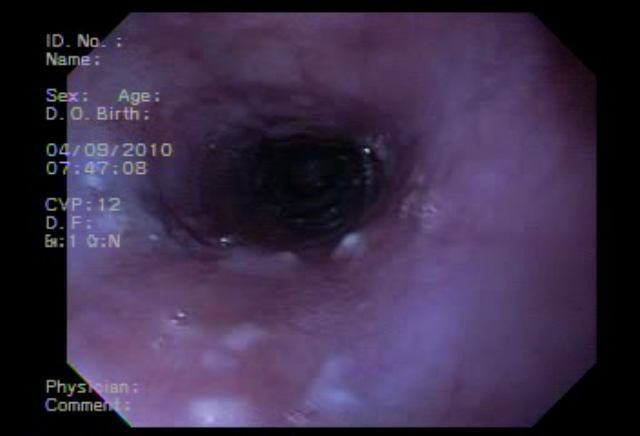

Cándida Esofagica |

Cáncer de Colon |

Gastropatia Severa |